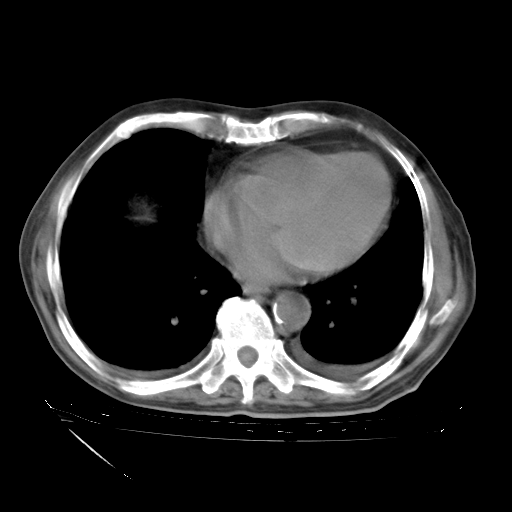

经过24天治疗,岳父的病情基本稳定。生活基本可以自理,可以下床活动。呼吸困难早已消失。体温基本正常。

只是甲强龙用80mg时血小板升到正常,改为60mg后又降到63×10*9/L。

主要治疗甲强龙80mg×14天,60mg×10天;同时抗结核(异烟肼+利福平+乙胺丁醇)。环磷酰胺0.1 tid 10天。

特别感谢胡教授、高管、桃子版主给出关键的治疗建议。桃版把所有肺部影像和全部临床资料请所在医院呼吸科、感染病科、结核科、临床免疫科专家会诊。临床免疫科专家制定了完整的治疗方案。